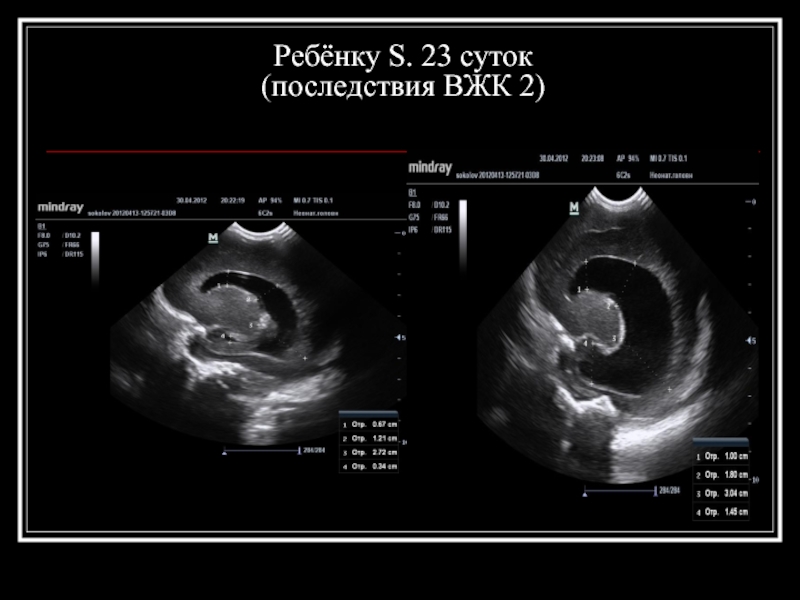

Слайд 16Ребёнку S. 23 суток (последствия ВЖК 2)

Слайд 17Ребёнку S. 23 суток (последствия ВЖК 2)